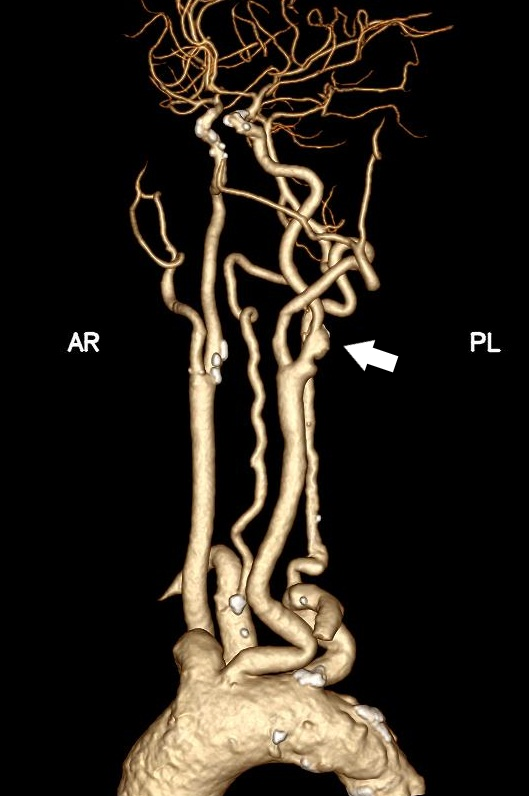

据悉,患者张某(化姓)因反复头晕就诊,检查后确诊为左侧颈内动脉重度狭窄,且主动脉弓为III型弓,颈总动脉明显迂曲,且左侧颈动脉分叉位置较高,属于颈动脉狭窄治疗中较为复杂的解剖类型。若采用传统经股动脉颈动脉支架置入术,导管通过主动脉弓及扭曲血管难度大,脑栓塞风险高;若行颈动脉内膜剥脱术,则会因为分叉位置高、术野暴露困难,手术创伤和技术难度也明显增加。

针对患者复杂病情,烟台毓璜顶医院血管外科团队在车海杰主任的带领下,开展了多轮术前讨论。在与患者及家属充分沟通后,最终确定采用国际前沿的TCAR技术实施治疗。手术当天,团队通过颈部小切口精准暴露颈总动脉,快速建立反转脑血流保护系统,在全程有效脑保护下完成病变段支架精准植入。术中造影显示,患者狭窄的颈内动脉恢复通畅,支架位置贴合理想,脑部供血得到显著改善。术后患者恢复顺利,无任何新发神经系统并发症,头晕等不适症状明显缓解,目前已顺利康复。

手术前后